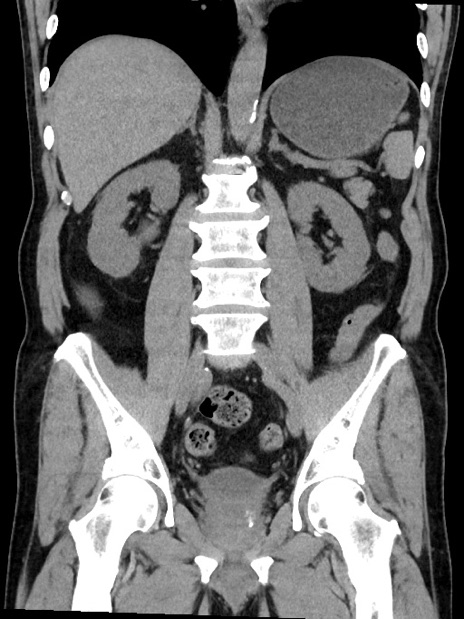

症例35(冠状断像)

【症例】70歳代 男性

【主訴】腹部膨満、嘔吐

【現病歴】昨日より腹部膨満感出現。本日増悪し、仙痛出現。嘔吐あり、受診。

【既往歴】糖尿病、胆摘後

【身体所見】BP 149/80mmHg、HR 74/min、BT 35.9℃、腹部:膨満、軟、圧痛なし。腸雑音減弱あり。上腹部正中切開瘢痕あり。

【データ】WBC 13500、CRP 1.72